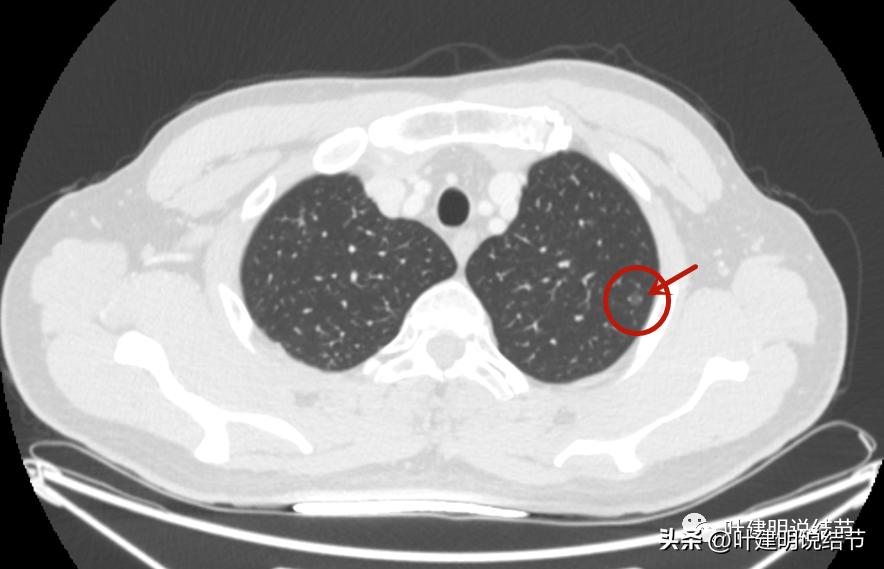

冠状位见多角度多边有血管贴着,磨玻璃部分密度低,轮廓清。

矢状位见病灶密度低,轮廓清,瘤肺边界清楚。